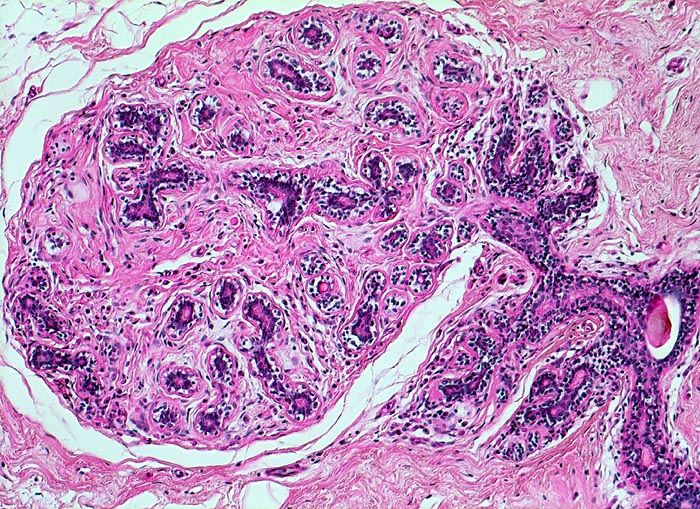

PathoPic ID 4661 - ruhende Mamma: normales Brustdrüsenläppchen

ruhende Mamma: normales Brustdrüsenläppchen

Scharf begrenztes Mammaläppchen mit

Tubuli. Diese werden drainiert durch einen

Ductus lactiferus.

Das ruhende Mammaläppchen enthält lediglich Tubuli. Die Mamma lactans besteht aus tubuloalveolären Drüsen.

Histologie

100

42